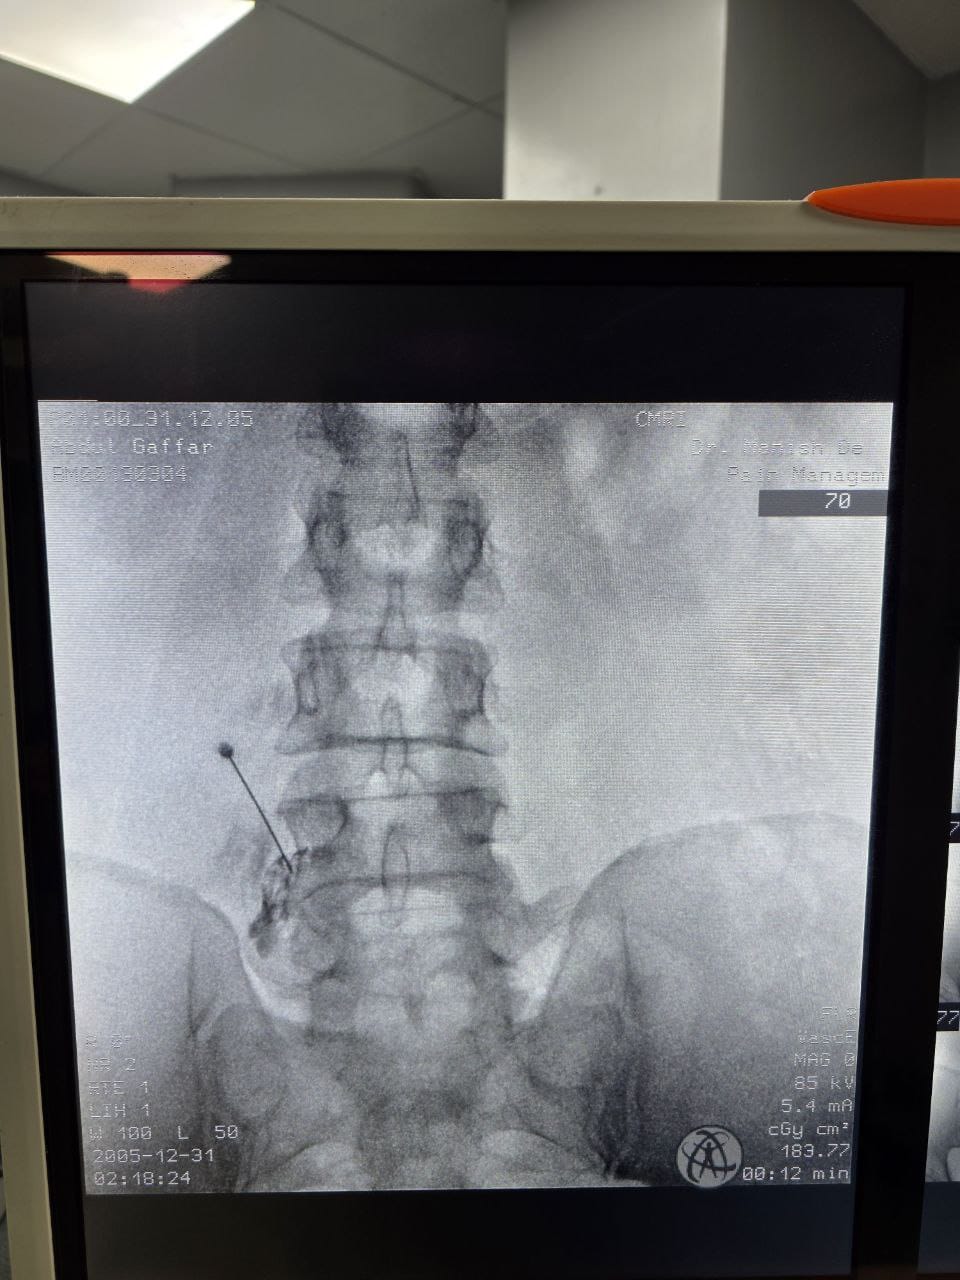

Procedures

Struggling with chronic pain? Get advanced, personalised pain management from Dr. Manish De, one of Kolkata’s leading pain specialists. From knee pain, heel pain, low back pain, frozen shoulder, migraines, cancer pain to post-TKR persistent pain—Dr. De offers safe, evidence-based treatments across multiple locations: